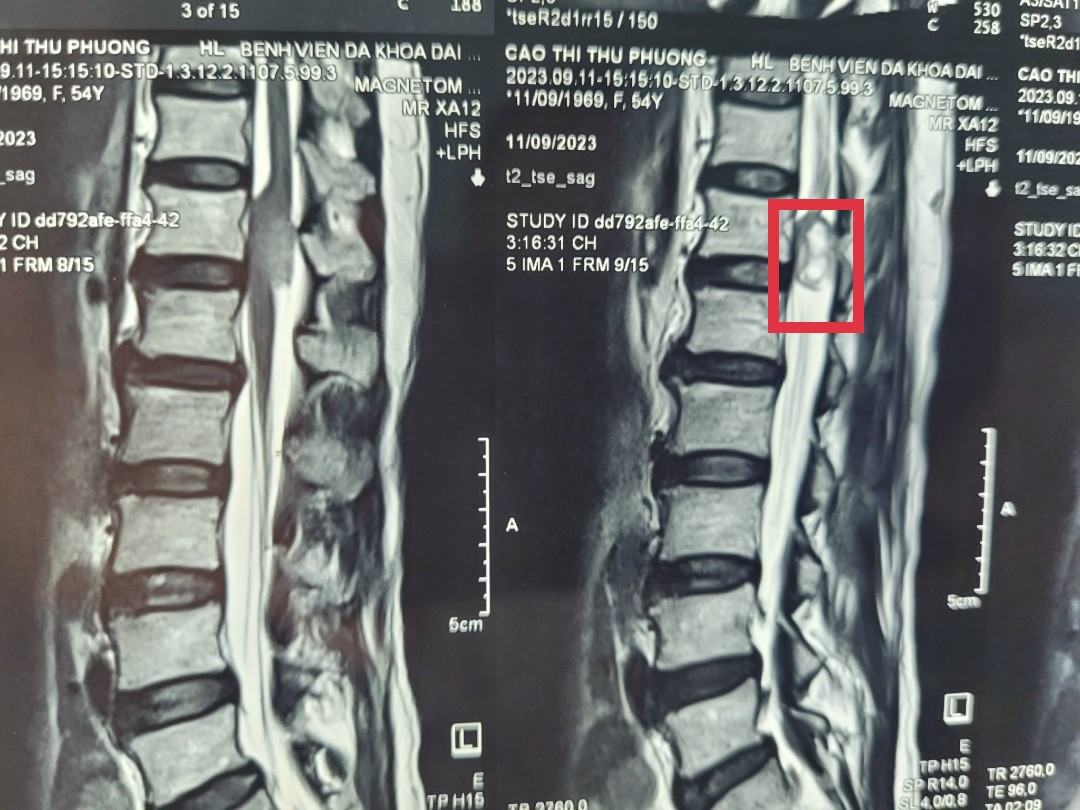

Tại đây, bệnh nhân được làm các xét nghiệm cận lâm sàng. Kết quả chụp Cộng hưởng từ (MRI) cho thấy khối u tủy sống D12, L1 kích thước 0.8x2cm chèn ép lên ống tủy gây hẹp ống sống. Bệnh nhân được chỉ định phẫu thuật lấy khối u, giải phóng chèn ép lên ống tủy.

Hình ảnh khối U tuỷ sống trên phim chụp MRI